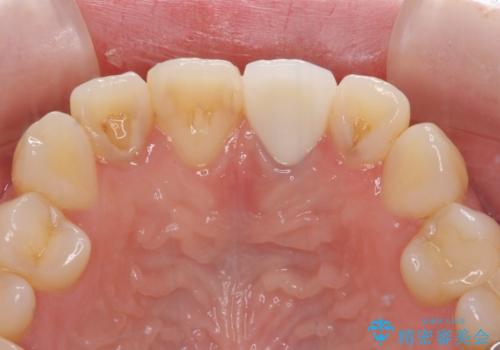

- 前歯のクラウン付近の歯肉が黒く見えることを気にして来院された患者様です。

根管治療を行った後に、オールセラミッククラウンにて補綴することとしました。